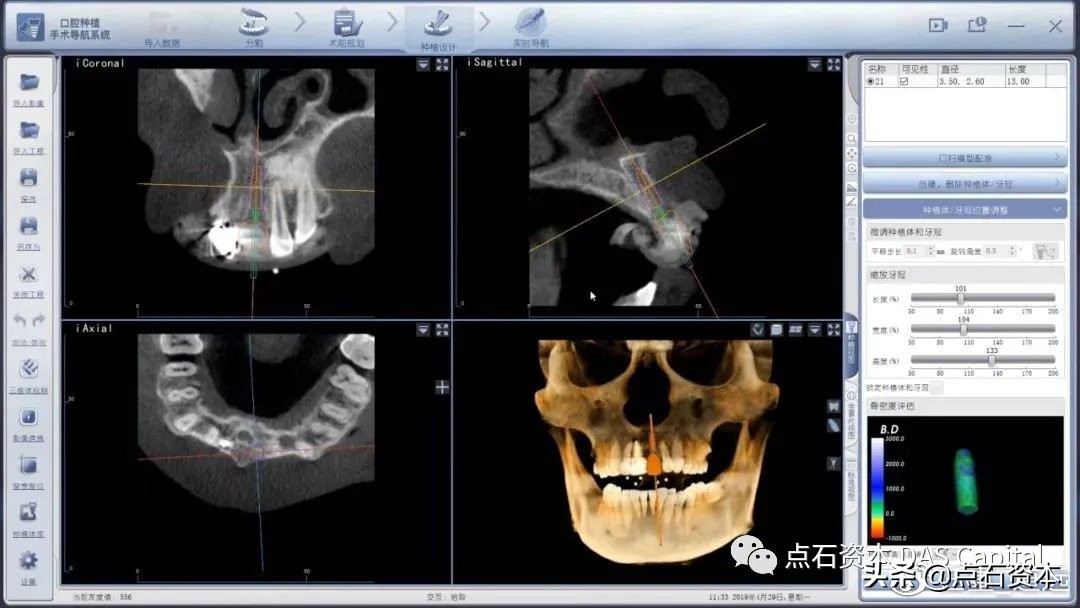

静态导板辅助治疗在临床应用中仍然面临一系列困境,例如备板产生的额外时间及成本,术中导板不可视,既定方案不可变更等。动态导航技术应运而生,进入2010年以后,逐渐在世界范围内成为临床种植的新宠儿。该技术帮助患者摆脱了术中对辅助导板的依赖,通过在患者口中建立标记点,将真实结构转化为计算机显示器上的三维坐标。因此,医生在术中可实时跟踪器械尖端的位置及路径,观察尖端周围的解剖结构,并在术中灵活地调整手术方案。近年来,多个临床试验相继证实,数字化动态导航技术的操作偏差在位点1mm,根尖部1mm,角度3.5°以下,较静态导板技术仍有一定提升。更为重要的是,导航技术节约了患者注册时间,进一步优化了手术体验。截止到2019年,动态导航系统已经完成了从简单到高度复杂的病例适应症全覆盖,全年临床比例数同比增长300%。

图9:医生在动态导航辅助下能够清晰观察腔内结构,随时调整方案